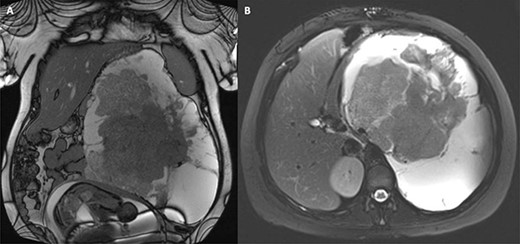

She was transferred to ICU at the regional sarcoma centre and was taken to theatre as an emergency case. The tumour was resected from her left retroperitoneum en bloc with the pancreatic body and tail (site of origin), spleen, a portion of the greater curvature of the stomach, left kidney and adrenal gland, the splenic flexure of the colon and a cuff of the left diaphragm. Simple excision was attempted but was abandoned in favour of multivisceral resection to preserve the integrity of the tumour and avoid spillage of cancerous cells, allowing the best chance of curative excision. Histopathology confirmed a large (35 cm, 8 kg) SPN which had been completely excised with clear margins (Fig. 2).

Peri-operative images showing (A) fresh specimen from multivisceral resection with spleen, pancreas and colon clearly visible, and (B) operative field after resection.